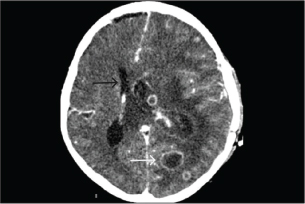

On day 28 of combination antifungal therapy, the patient experienced a severe left temporal headache accompanied by motor weakness (grade III on the right side and grade IV on the left side). Repeat brain CT demonstrated progression of abscesses, left lateral ventriculitis, increased vasogenic edema, and uncal herniation (Fig. 4). The patient was deteriorating, and there was significant brain swelling. A third neurosurgical intervention involving left decompressive craniectomy with duraplasty and EVD placement was performed to relieve intracranial pressure. Postoperatively, the patient showed slight improvement in motor function and maintained normal consciousness.

Fig. 4. A computed tomography scan of the brain with contrast on day 28 of antifungal treatment showed increased size of some abscesses (white arrow), ventriculitis of the left lateral ventricle, increased vasogenic edema, and midline shift to the right (black arrow).